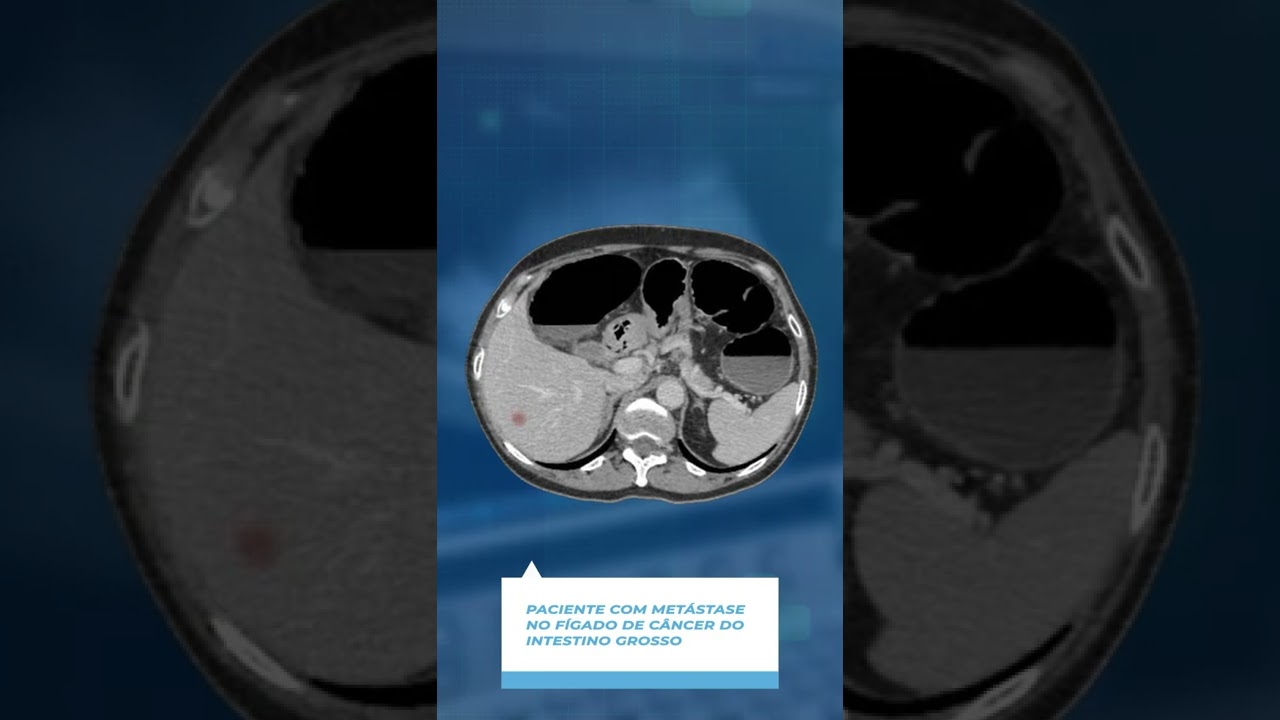

Tenho dedicação especial à cirurgia hepática e ao transplante de fígado, participando de equipes especializadas no manejo de doenças hepáticas avançadas e tumores hepáticos. Nessa área, atuo no tratamento multidisciplinar de condições como carcinoma hepatocelular, metástases hepáticas, colangiocarcinoma e outras doenças do fígado.

Metástases hepáticas

Cirurgia de metástases hepáticas